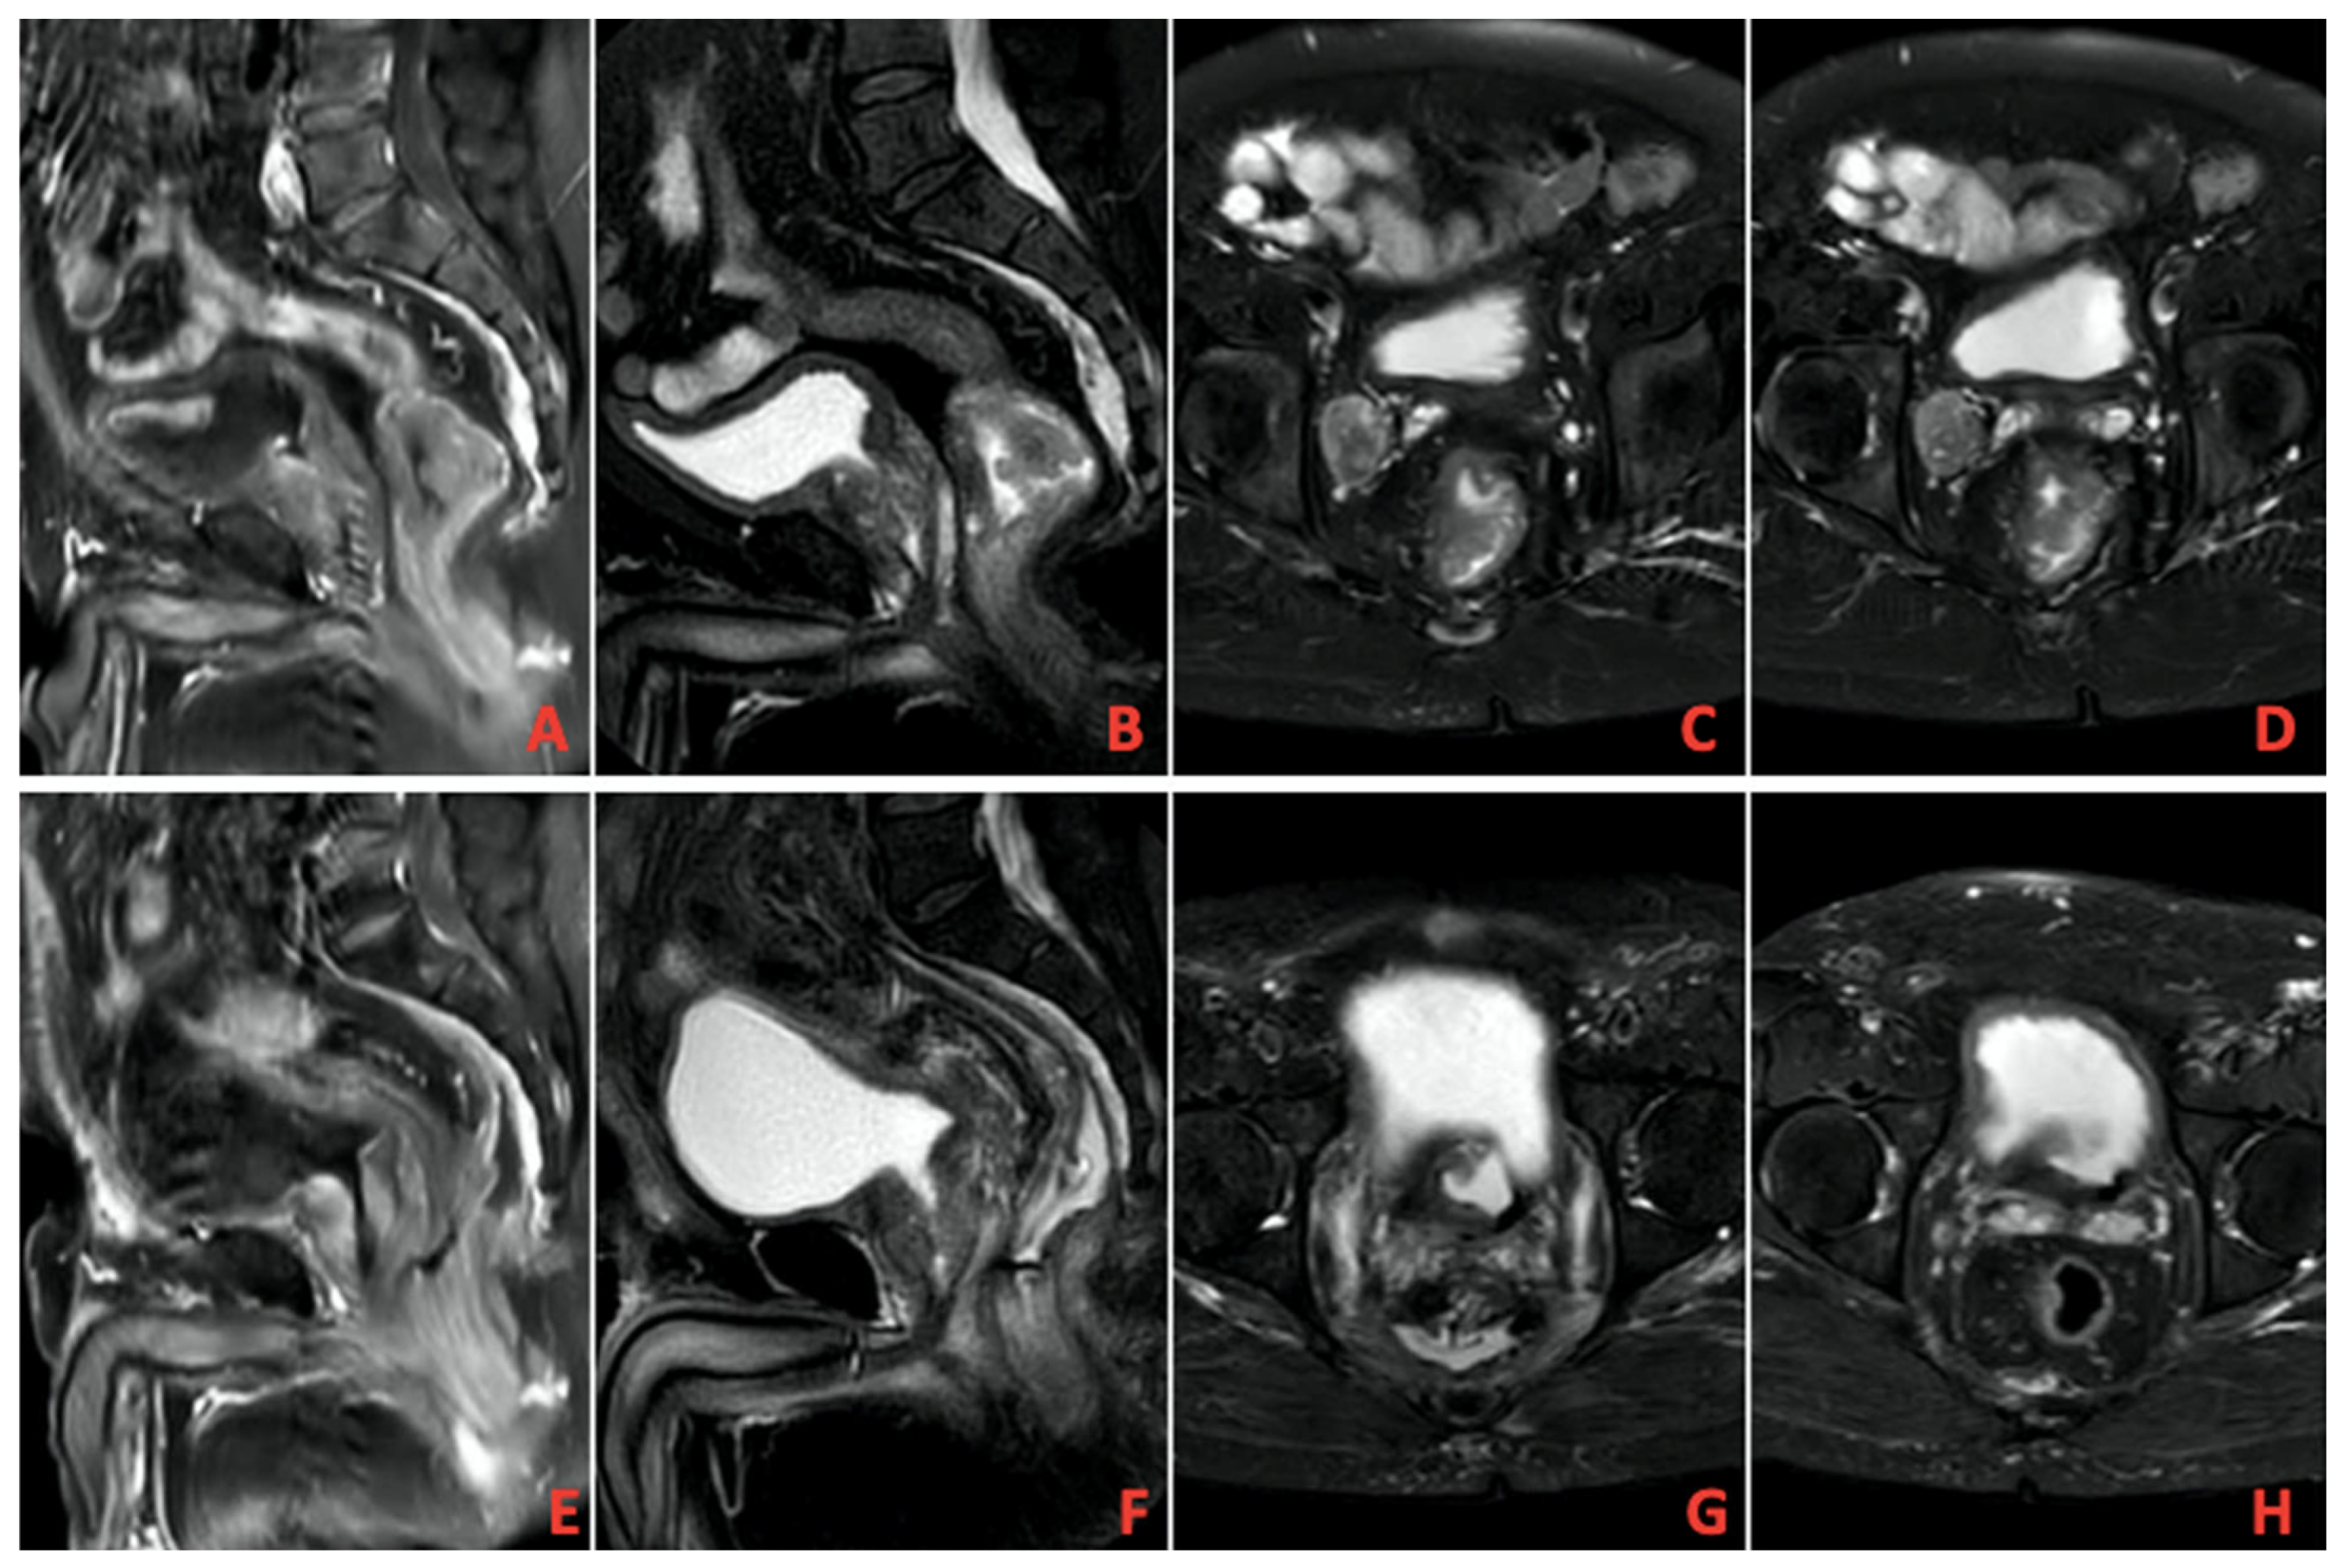

A total of 13 patients evaluated as cCR after TNT was completed were followed up with NOM. Figure 1 shows MRI images of a patient with complete response, and Figure 2 shows PET/CT images. It shows that 39 patients underwent surgery, and 8 of them had pCR. A total of 9 patients had ypT0 (one of them was ypT0N1), 1 had ypT1, 6 had ypT2, 21 had ypT3, and 1 had ypT4. In addition, 27 patients had no pathologically involved lymph nodes (ypN0), 9 had ypN1, and 2 had ypN2. These findings and tumor regression grading distribution are summarized in Table 3.

Figure 1. (AD) Pretreatment imaging, (EH) Posttreatment imaging on magnetic resonance imaging (MRI).